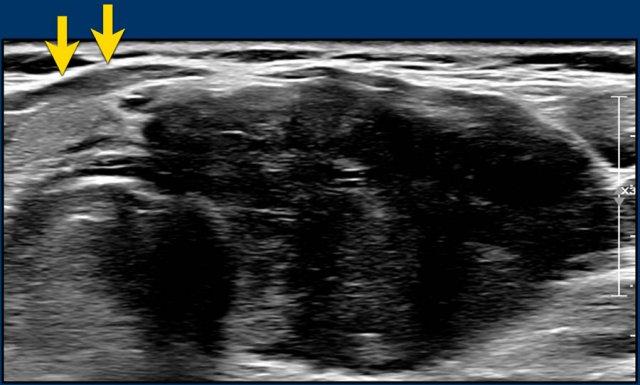

Tổn Thương Giảm Âm Rõ Rệt

Tổn thương giảm âm rõ rệt có độ hồi âm thấp hơn so với mô cơ bình thường.

Lưu ý rằng, trong hình ảnh được cung cấp, tổn thương có độ giảm âm cao hơn so với các cơ dải (được chỉ bởi các mũi tên).